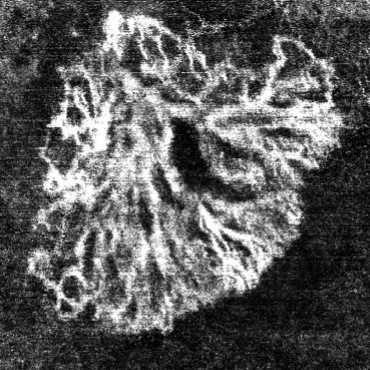

Knowing that an OCTA image has a scale of and that each OCTA image contains pixels, we find the size of one pixel to be 0.154 . The original image after the ”Image Processing” phase focuses on the blood vessel area, represented by the white pixels. It indicates the size of the active mCNV lesion. The internal black areas show parts of the object where the blood vessel is missing. Figure 8 illustrates a structure similar to a sponge.

To calculate the total area, we need to pass the output image from the ”Image Processing” phase through another operation, Region Fill, to fill in the black missing sections from the initial binary image. After applying this filter, the total vessel area will be larger than the mCNV area: .

Feature combination is then applied to compute the Vessel Density, which is the ratio of the mCNV Area to the Total Area: .